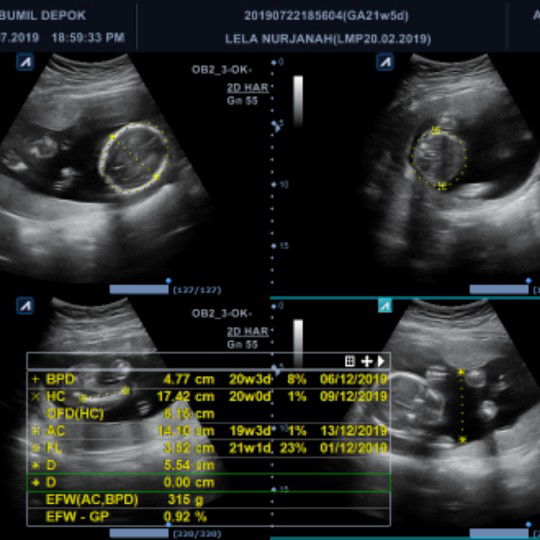

USIA KEHAMILAN

bunda mau tanya, kemarin saya usg dan cara baca usg itu gimana yaa?? saya pengen tau pasti berapa usia kehamilan saya.. kalau saya itung sendiri si jalan 6bulan bunda.. bener gak yaa??